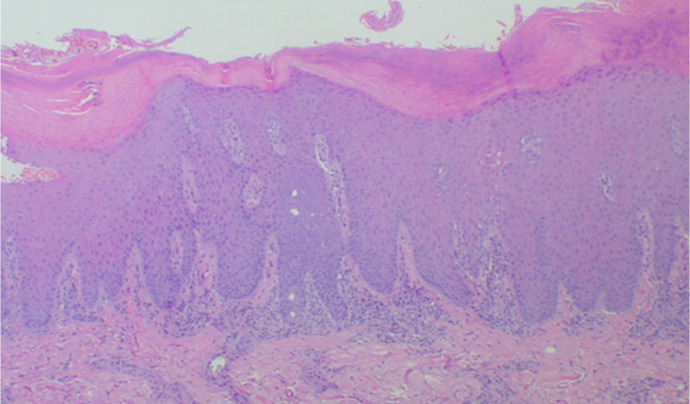

Introduction: Psoriasis is a chronic systemic inflammatory disorder resulting from complex interactions between genetic and environmental factors. In addition to cutaneous manifestations, psoriasis is associated with psoriatic arthritis (PsA). Among the recognized mechanisms of disease exacerbation, the Köbner phenomenon (KP) plays a crucial role. KP refers to the appearance of new psoriatic lesions on previously healthy skin following trauma. A deeper variant of this phenomenon, the deep Köbner phenomenon (DKP), involves severe trauma triggering systemic inflammation, including the onset of PsA. Trauma-induced DKP represents unique disease mechanisms, linking external mechanical stress to immune-mediated joint pathology.

Case presentation: We present a case of a 60-year-old male with psoriasis, who initially responded well to ixekizumab, an IL-17A inhibitor but subsequently developed PsA following a wrist injury. The PsA exacerbation was attributed to increased mechanical stress from daily activities and rehabilitation efforts. Adjustments were made to rehabilitation intensity and joint movement restrictions, leading to gradual symptom improvement over 3 months without intensifying biological therapy.